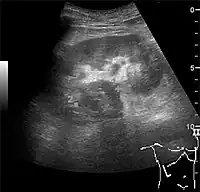

Hydronephrosis

One of the primary indications for referral to US evaluation of the kidneys is evaluation of the urinary collecting system. Enlargement of the urinary collecting system is usually related to urinary obstruction and can include the pelvis, the calyces and the ureter. Hydronephrosis is seen as an anechoic fluid-filled interconnected space with enhancement within the renal sinus, and normally, the dilated pelvis can be differentiated from the dilated calyces.[1]

Several conditions can result in urinary obstruction. In both adults and children, masses, such as abscesses and tumors, can compress the ureter. In children, hydronephrosis can be caused by ureteropelvic junction obstruction, ectopic inserted ureter, primary megaureter and posterior urethral valve (Figure 13). In the latter, both kidneys will be affected. In adults, hydronephrosis can be caused by urolithiasis, obstructing the outlet of the renal pelvis or the ureter, and compression of the ureter from, e.g., pregnancy and retroperitoneal fibrosis. Urolithiasis is the most common cause of hydronephrosis in the adult patient and has a prevalence of 10%–15%.[1]

Under normal conditions, the ureter is not seen with US. However, in, e.g., urinary obstruction and vesicoureteric reflux with dilation of the ureter, the proximal part in continuation with the renal pelvis, as well as the distal part near the ostium can be evaluated (Figure 14).[1]

The hydronephrosis is typically graded visually and can be divided into five categories going from a slight expansion of the renal pelvis to end-stage hydronephrosis with cortical thinning (Figure 15). The evaluation of hydronephrosis can also include measures of calyces at the level of the neck in the longitudinal scan plane, of the dilated renal pelvis in the transverse scan plane and the cortical thickness, as explained previously (Figure 16 and Figure 17).[1]

If the fluid in the dilated collecting system has echoes, pyonephrosis should be excluded by clinical exam, blood analysis and, in special cases, puncture or drainage. Hydronephrosis can also be caused by non-obstructive conditions, such as brisk diuresis in patients treated with diuretics, in pregnant women and in children with vesicoureteral reflux.[1]

Figure 15. End-stage hydronephrosis with cortical thinning. Measurement of pelvic dilatation on the US image is illustrated by ‘+’ and a dashed line.[1]

Figure 16. Hydronephrosis with dilated anechoic pelvis and calyces, along with cortical atrophy. The width of a calyx is measured on the US image in the longitudinal scan plane, and illustrated by ‘+’ and a dashed line.[1]

Figure 17. Same patient as in Figure 16 with measurement of the pelvis dilation in the transverse scan plane illustrated on the US image with ‘+’ and a dashed line.[1]